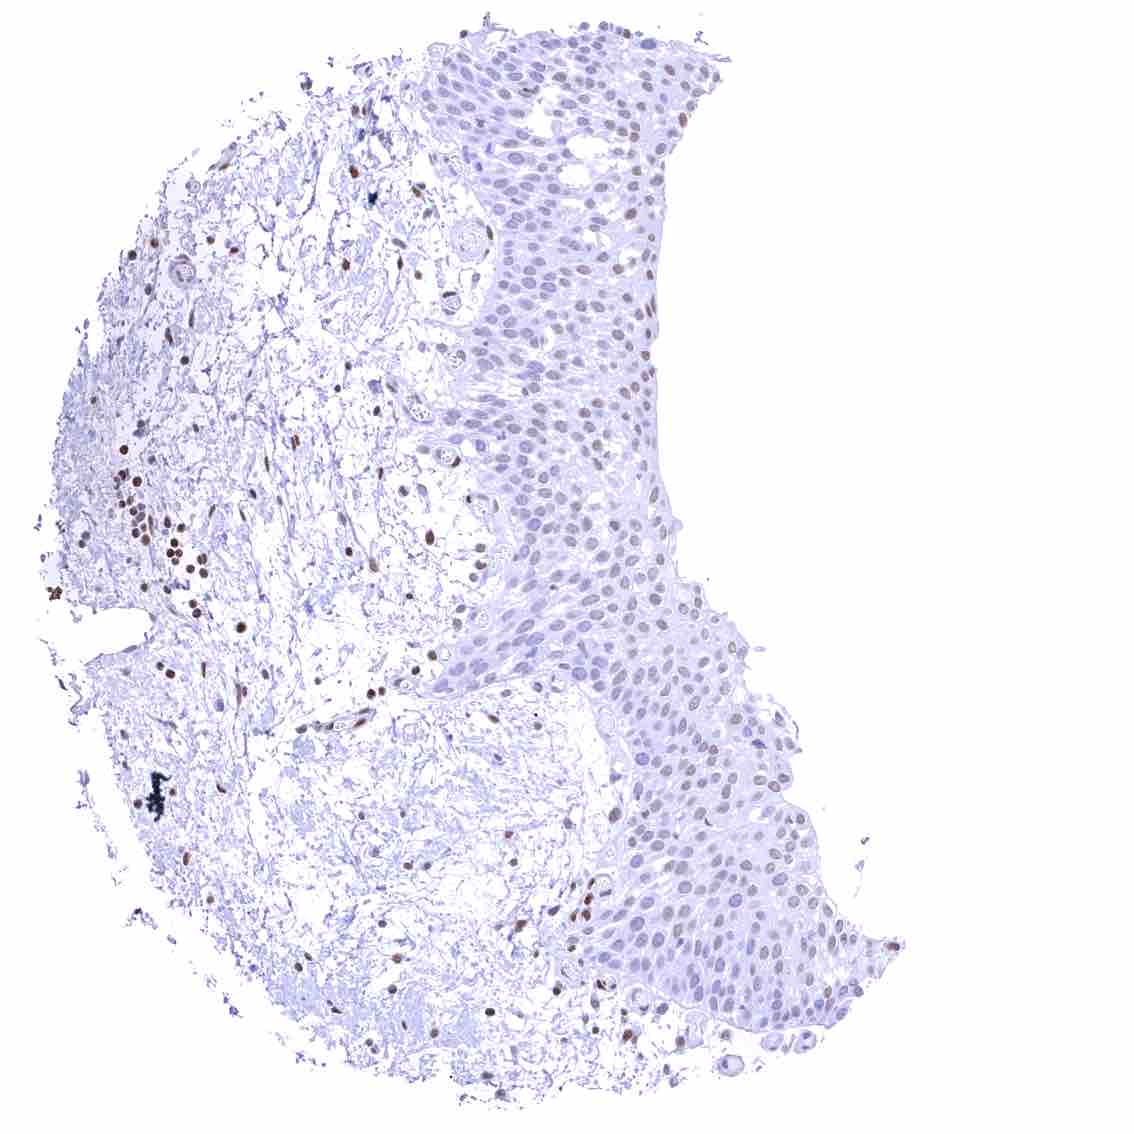

Tonsil – Strong nuclear p27 staining of a significant subset of cells, especially in the interfollicular area. Nuclear staining of squamous epithelial cells predominates in the more mature cell layers (top 50_ of the epidermis)

Tonsil, surface epithelium – Strong nuclear p27 staining of a significant subset of cells, especially in the interfollicular area. Nuclear staining of squamous epithelial cells predominates in the more mature cell layers (top 50_ of the epidermis)

Uterus, ectocervix – Nuclear staining of squamous epithelial cells predominates in the more mature cell layers (top 50_ of the epidermis).